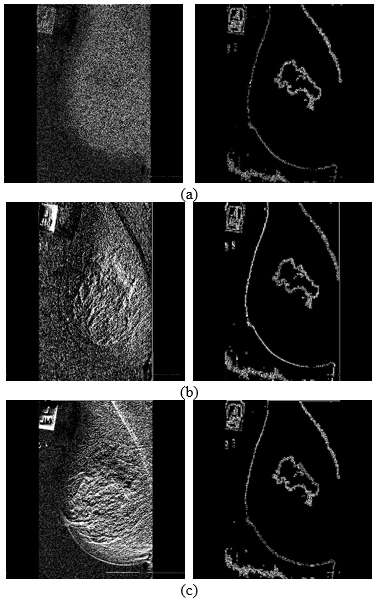

Figure 5 shows a few sample images obtained after segmentation.

The first step done is image segmentation based on the intensities of the mammogram images. K-means algorithm is used with adaptive noise removal to obtain the best results of segmentation. Image scan of mamogram is divided into portions and each portion is represented with a different gray level intensity. These different intensities extracts the features of ROI in the image. The abnormality or tumor can easily be detected in the segmented image.

4.1 Segmentation